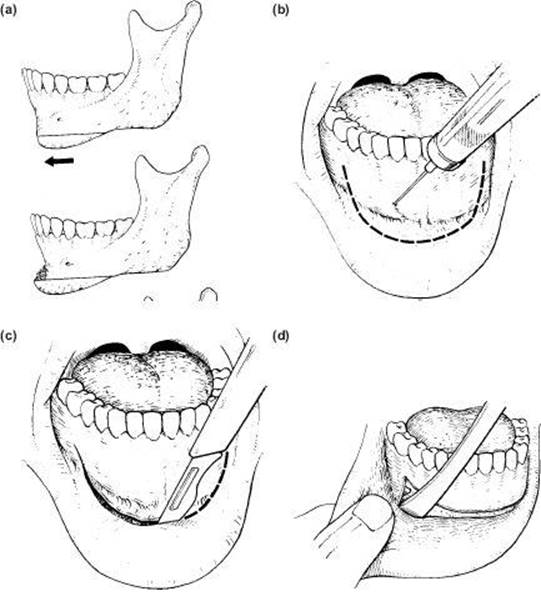

Technique (Figure 9.4)

1. A 5 cm submandibular or retromandibular incision is marked with a pen and infiltrated with 4 ml local anaesthetic containing 1:80,000 adrenaline. This is made in a skin crease two fingers' breadth below the mandibular border to avoid the marginal (mandibular) branch of the facial nerve. A lower crease requires a larger incision (Figure 9.4a). Note: Never mark an incision with the head rotated: this will produce unexpected changes in the surface anatomy.

5. The muscle and periosteum can now be incised along the lower border with a knife and stripped upwards to the sigmoid notch and coronoid process. The Obwegeser channel or Robertson ramus retractor may be hooked over the notch to expose the ramus (Figure 9.4b).

6. A small buccal prominence is a reasonably accurate landmark of the lingula area, so a cut downwards and behind this from the midpoint of the sigmoid notch to the beginning of the curve of the angle avoids the inferior dental neurovascular bundle. This may be done with a fissure bur or reciprocating saw. A flat retractor should be placed on the medial aspect of the ramus to protect the soft tissues.

Figure 9.4 (a), (b), (c), (d), (e)

7. Once separated, the inner cortex of the narrow fragment and the outer cortex of the main segment may be bevelled with an acrylic bur to ensure good opposition.

8. For large distal displacements, i.e. greater than 0.7 cm, it is necessary to do a coronoidectomy to remove the restraining influence of the temporalis muscle (Figure 9.4c).